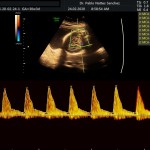

- La vitalidad y el bienestar fetal (Doppler).

- El Doppler de las arterias uterinas maternas y determinación de riesgo para pre eclampsia severa.